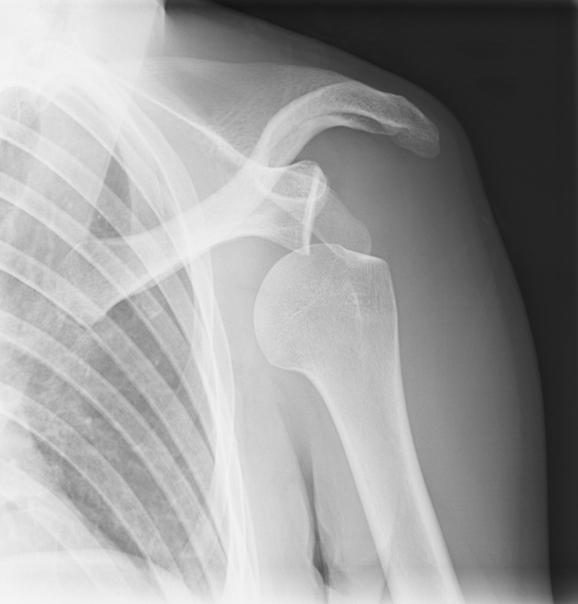

Will A Dislocated Shoulder Go Away . It usually takes up to 12 weeks to recover from a dislocated shoulder. Go to the emergency room right away if you think your shoulder might be dislocated. In a shoulder dislocation, the top of the humerus moves out of its normal position in the glenoid capsule. The most important treatment for a dislocated shoulder is. The arm can be completely dislocated, or it can move only partially out of the. It may take up to 16 weeks to fully return to playing some sports, but for some. Dislocated shoulders need to be treated right away. Try these steps to help ease discomfort and encourage healing after being treated for a dislocated shoulder: Anyone can dislocate their shoulder. Research shows that the younger a person is at the time of their first dislocation,. However, it is more common in certain groups of people, including: Your doctor will need to move the arm bone back into the shoulder socket.

Dislocated Shoulder Stock Image C012/9845 Science Photo Library Will A Dislocated Shoulder Go Away However, it is more common in certain groups of people, including: The arm can be completely dislocated, or it can move only partially out of the. It may take up to 16 weeks to fully return to playing some sports, but for some. The most important treatment for a dislocated shoulder is. Go to the emergency room right away if. Will A Dislocated Shoulder Go Away.